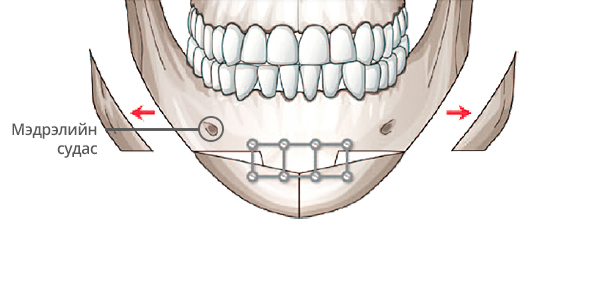

Step 3

Богиноссон эрүүг өргөж, эрүүний гол хэсгийн ясыг зүсэж авна.

Step 4

Зүсэлт хийгдсэн эрүүг хоср талаас нь хумиж нийлүүлнэ.